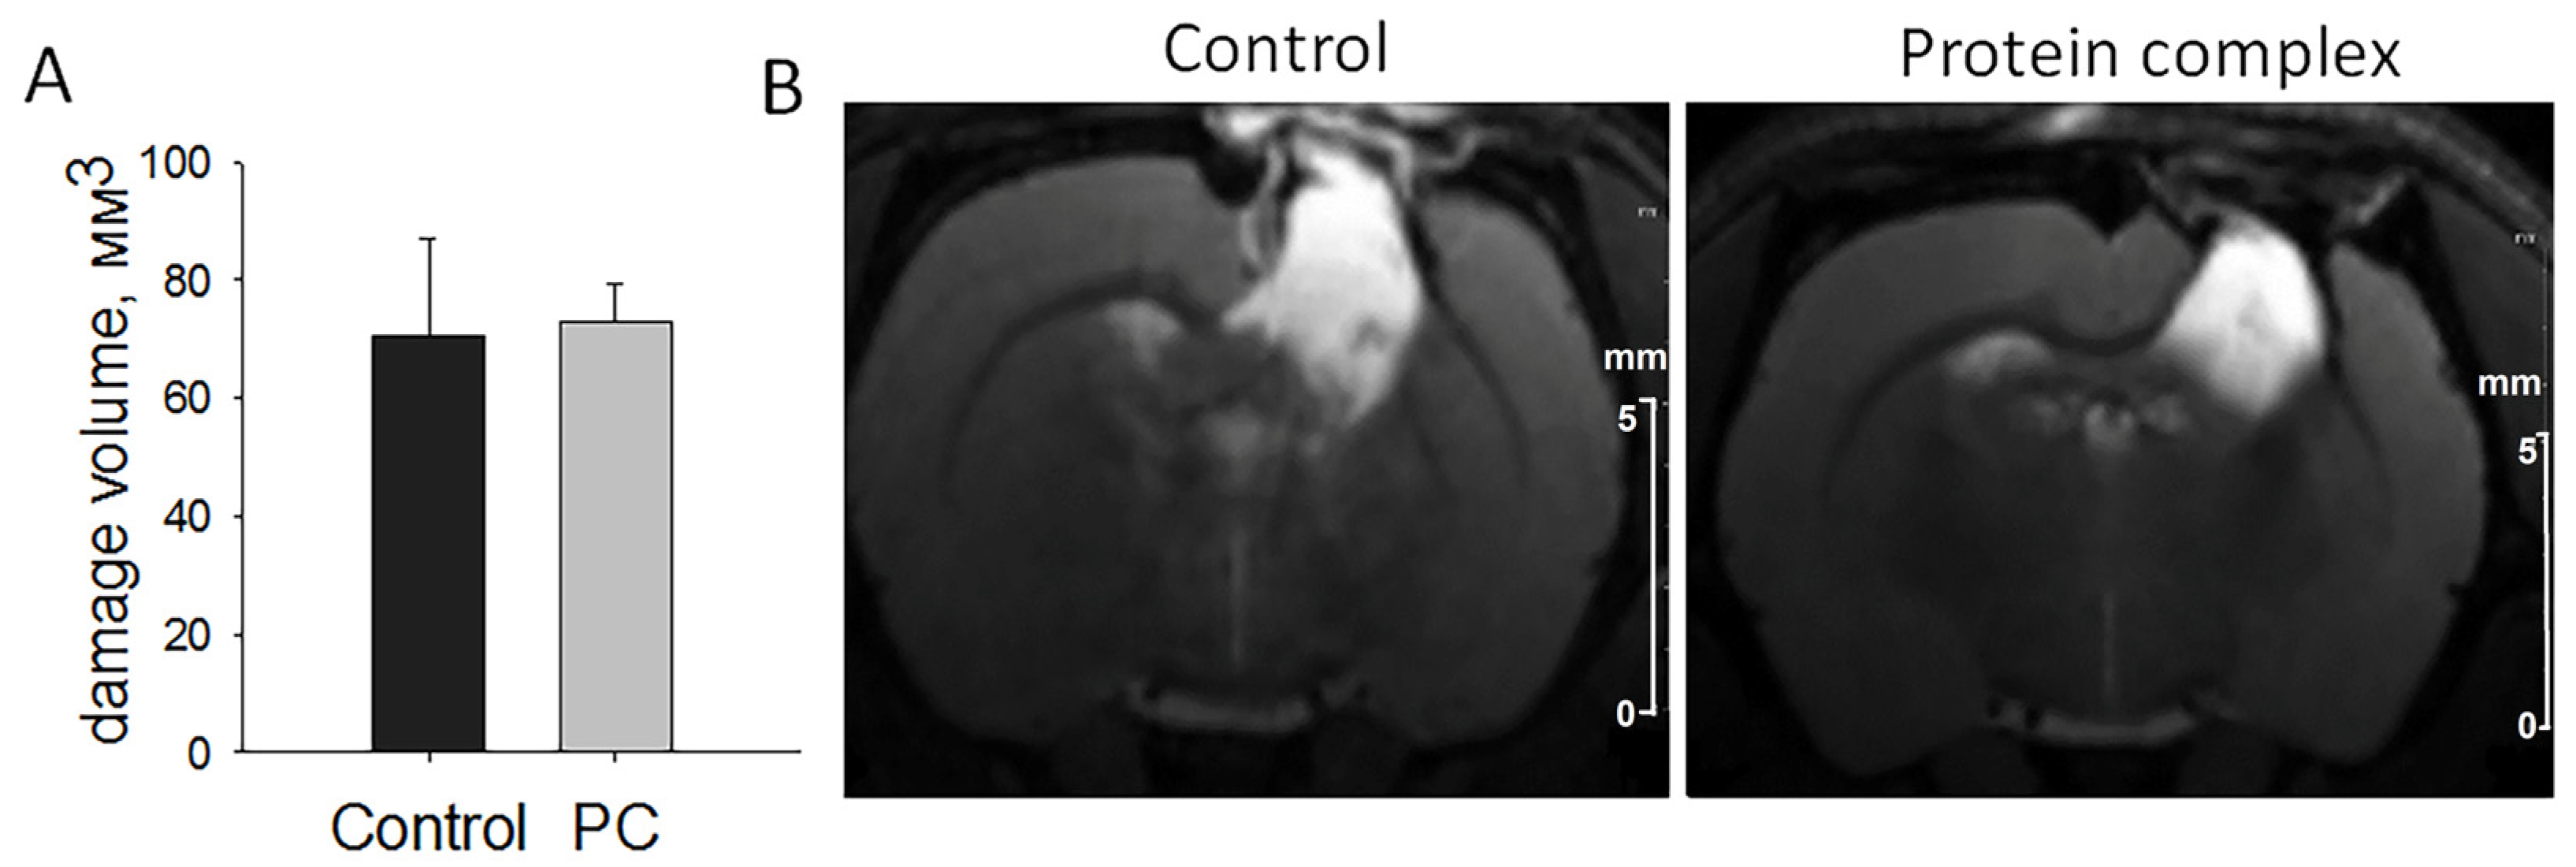

2.2. Assessment of Damage Volume